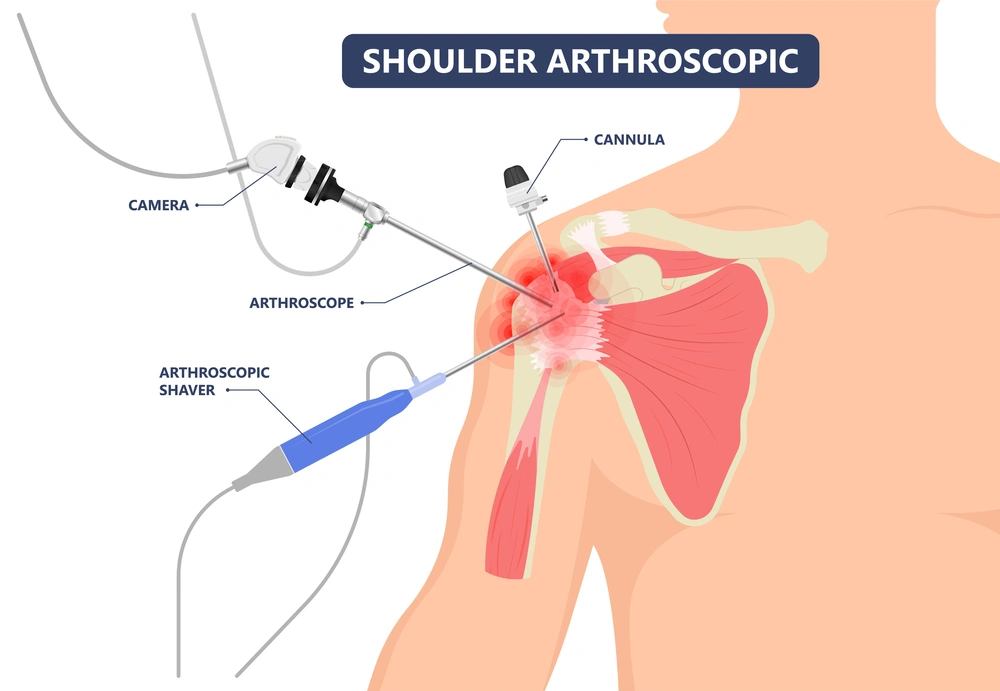

Cartilage repair procedures are often minimally invasive, performed through small arthroscopic incisions using advanced imaging and surgical navigation systems. Microfracture surgery stimulates new cartilage growth by creating small holes in the underlying bone, while ACI involves growing healthy cartilage cells in a lab before implanting them in the damaged area. Osteochondral grafting replaces damaged tissue with healthy cartilage and bone from the patient or donor. Recovery includes early physical therapy to restore strength, flexibility, and range of motion, with gradual progression of weight-bearing under professional supervision. Most patients experience significant improvement in function and reduction in pain within weeks to months, depending on the procedure and extent of damage.